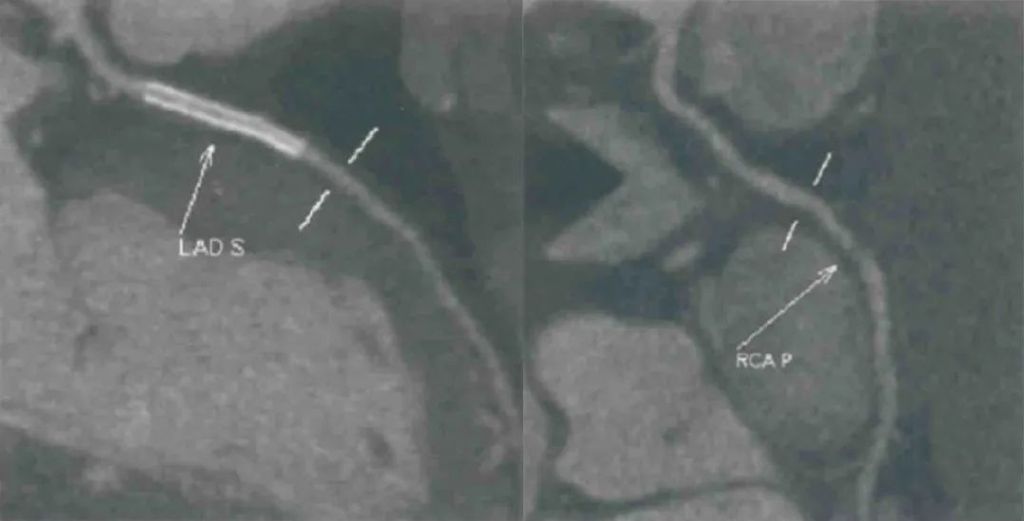

患者曾于2019年10月行冠状动脉造影检查,发现前降支近中段狭窄90%,右冠状动脉狭窄60%,回旋支、左主干未见明显狭窄,于前降支植入支架(图4)。

图4. 2019年10月行冠状动脉造影(上下滑动查看)前降支近中段狭窄90%,右冠状动脉狭窄60%,回旋支、左主干未见明显狭窄,于前降支植入支架

术后常规双联抗血小板治疗。2020年9月门诊复查冠状动脉CTA示:前降支支架通畅,右冠状动脉狭窄约80%,未予处理(图5)。

图5. 2020年9月门诊复查冠状动脉CTA前降支支架通畅,右冠状动脉狭窄约80%